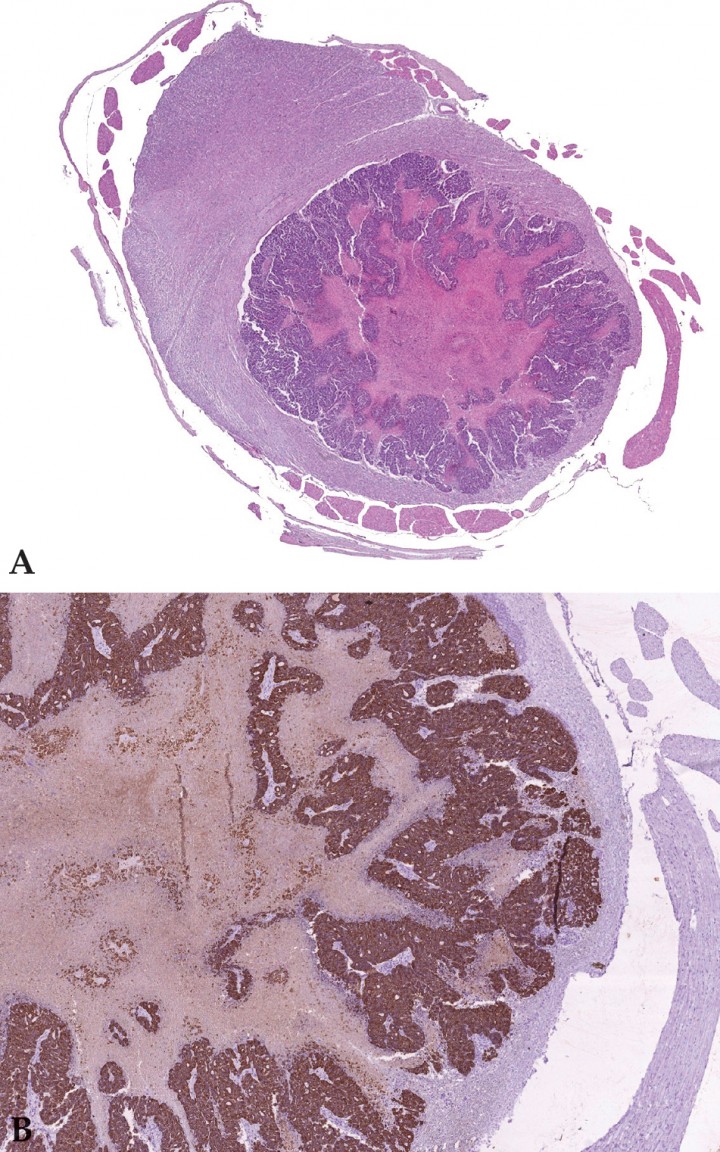

En la necropsia se observaron múltiples nódulos subcutáneos, blancos, firmes de 0,2 a 2 cm de diámetro en región lumbar, región esternal, espacios intercostales y glándulas mamarias e intramusculares de similar morfología. No se observaron lesiones macroscópicas en médula o columna vertebral. En el estudio histológico se observó que la mayor parte de la glándula mamaria había sido reemplazada por una neoplasia maligna no encapsulada, bien circunscrita, compuesta de células epiteliales dispuestas en cordones y túbulos (Fig. 1A). En algunas áreas, las células epiteliales se disponían en patrones sólidos con un gran centro necrótico (Fig. 1B). El índice mitótico y la anisocariosis eran elevados, observándose invasión de las células neoplásicas a vasos linfáticos y sanguíneos. En base a estos hallazgos se diagnosticó un carcinoma tubulopapilar simple, con áreas de comedocarcinoma, de alto grado (grado III).[ Mills SW, Musil KM, Davies JL, Hendrick S, Duncan C, Jackson ML, et al. Prognostic value of histologic grading for feline mammary carcinoma: a retrospective survival analysis. Vet Pathol, 2015; 52(2): 238-249. [PubMed] ] En el pulmón y músculo esquelético de los miembros posteriores, se observaron focos neoplásicos, muchos de ellos mostrando un patrón de comedocarcinoma (“nidos” sólidos con focos necróticos) (Fig. 2). Asimismo, había una evidente invasión vascular, principalmente en pequeñas arteriolas (Fig. 3). Se observó un nódulo metastásico grande, bien circunscrito, no encapsulado en la médula espinal (segmento L1-L2). Las células neoplásicas, que mostraron morfología de comedocarcinoma, expandían la sustancia blanca y comprimían la gris (Fig. 4A). Por su parte, las células neoplásicas presentes en todos estos órganos eran intensamente positivas para citoqueratina y negativas para vimentina y actina, lo que es consistente con un diagnóstico de carcinoma simple (Fig. 4B).

<p>Imagen microscópica de la glándula mamaria. (A) Carcinoma mamario mostrando un patrón tubulopapilar (HE 100x). (B) Áreas de comedocarcinoma (HE 200x).</p>

Imagen microscópica de la glándula mamaria. (A) Carcinoma mamario mostrando un patrón tubulopapilar (HE 100x). (B) Áreas de comedocarcinoma (HE 200x).